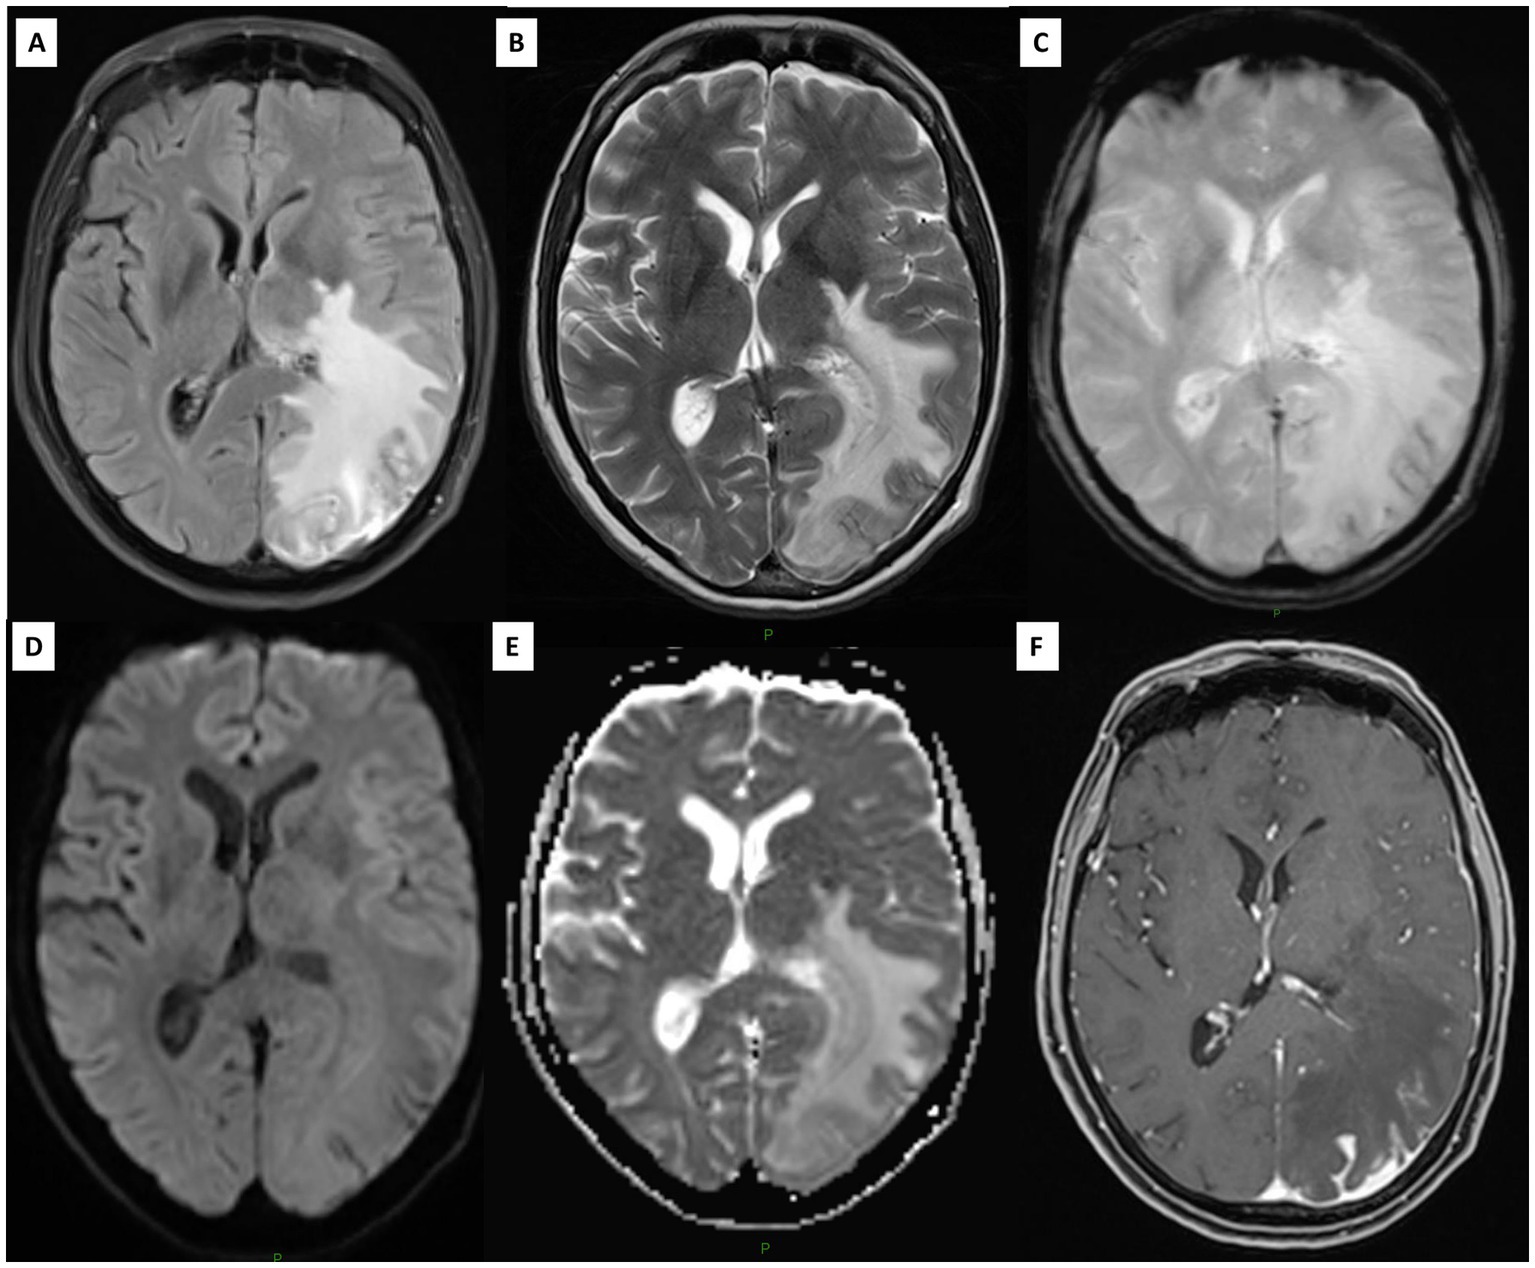

Imaging analysis revealed more often the presence of a pseudotumoral lesion at diagnosis in PACNS (45% vs. 10%, p = 0.014) and all patients with PACNS had negative [18F]FDG-PET/CT (p < 0.001) (Figure 2). No differences were found in the presence of atrophy, periventricular/white matter hyperintensities, microbleeds, intracranial arterial beading or stenosis location on MRA. Small-size vessel involvement was the most representative pattern in both primary and secondary CNS angiitis (Figure 3 and Supplementary Table 1). For PACNS, 12 cases were biopsy-diagnosed and 8 imaging-diagnosed. For SACNS, 6 cases were biopsy-diagnosed and 14 imaging-diagnosed.

Figure 2. Brain MRI showing a pseudotumoral lesion in the left hemisphere. (A) Axial FLAIR and (B) T2-weighted imaging. (C) T2*-weighted imaging demonstrates a small intralesional hemorrhage (D,E) DWI and ADC confirm vasogenic edema of the lesion. (F) After gadolinium injection, parieto-occipital cortico-pial contrast enhancement is observed on the left side, with corresponding pachymeningeal thickening.